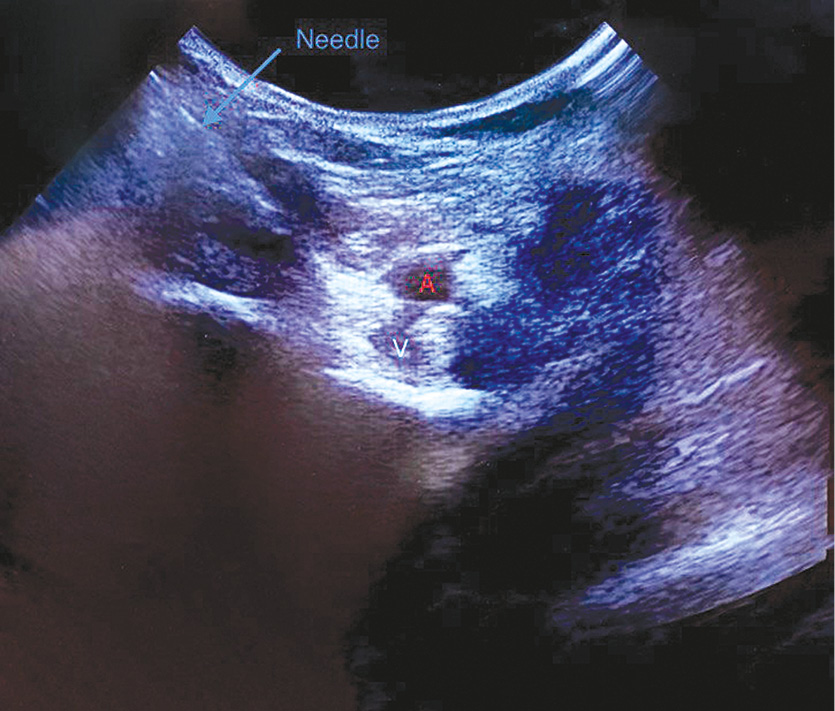

Также под контролем УЗ-навигации проводили инфильтрацию промежутка между подколенной артерией и задней частью капсулы коленного сустава (IPACK) — вводили 15 мл раствора ропивакаина (6,7 мг/мл; рис. 2). Далее непрерывное введение 0,5% ропивакаина по бедренному катетеру осуществляли со скоростью 6–8 мл/ч на протяжении 24 ч.

Рис. 2. Ультразвуковая картина при IPACK. A — подколенная артерия, V — подколенная вена.